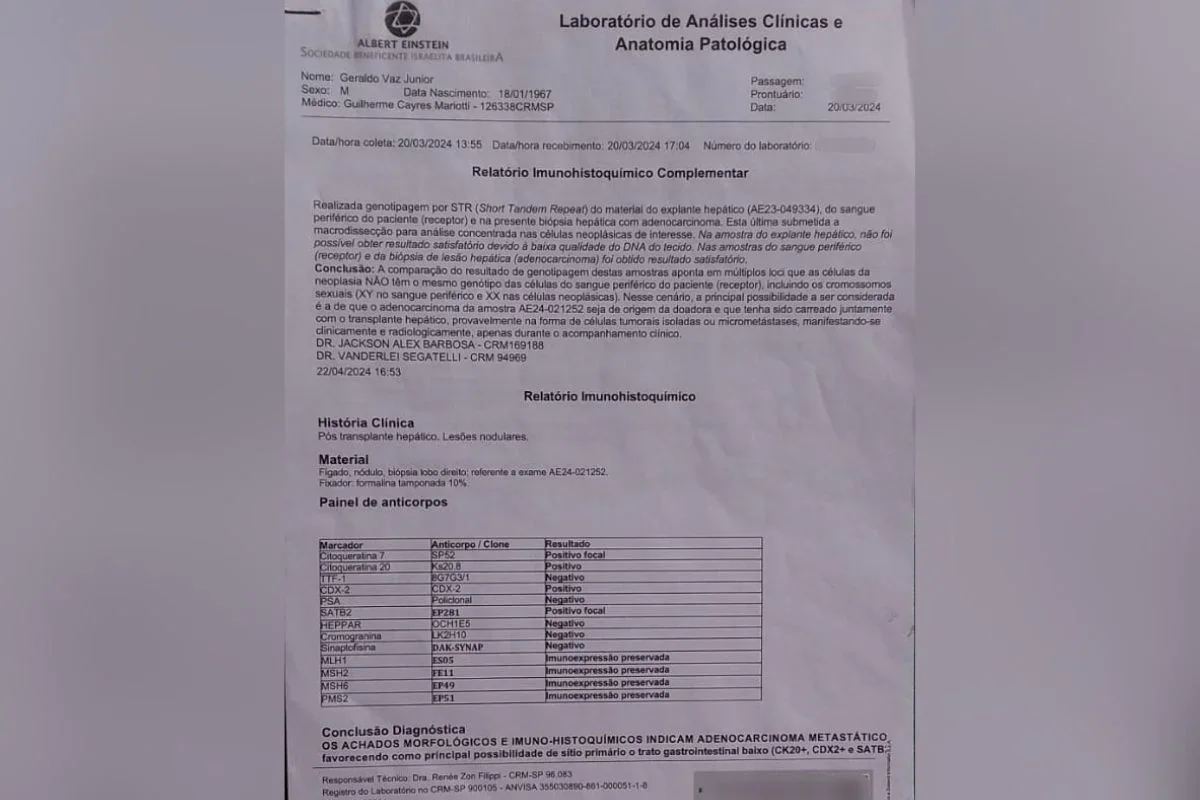

Geraldo Vaz Junior, de 58 anos, passou por um transplante de fígado em março de 2023, acreditando que seria o início de uma nova fase após enfrentar a hepatite C. No entanto, meses depois, exames revelaram que o órgão transplantado continha um adenocarcinoma, um tipo de tumor maligno. Pouco tempo depois, ele foi diagnosticado com metástase pulmonar do mesmo câncer.

A Secretaria Estadual de Saúde de São Paulo reforçou que os transplantes seguem critérios rigorosos, com exames clínicos e laboratoriais obrigatórios. O Hospital Albert Einstein, onde Geraldo é acompanhado, esclareceu que não participou da triagem do doador.

Especialistas afirmam que a transmissão de câncer em transplantes é extremamente rara, com incidência inferior a 0,03%, mas que o risco existe. O oncologista Paulo Hoff explicou que, apesar da triagem, tumores ocultos podem passar despercebidos. Segundo ele, o câncer veio do fígado transplantado, indicando que a doadora teve a doença em algum momento.